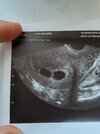

Chciałam się zapytać czy wiecie może czy na tym zdjęciu mogę już stwierdzić czy to ciąża bliźniacza dwujajowa czy jednojajowa?

Chyba mylisz pojęcia. Skoro podałaś link to może się z nim zapoznaj co oznacza ciąża jedno czy dwujajowa. Na zdjęciu są ewidentnie dwa oddzielne pęcherzyki. Nie są ze sobą powiązane. Więc jak najbardziej są to bliźniaki dwujajowe.

Na pewno statystycznie większa szansa, że będą dwujajowe, ale jednak pęcherzyki bezpośrednio do siebie przylegają więc ja bym nie miała pewności 100%. Dla porównania u mnie wyglądało to tak- zobacz że pęcherzyki są mocno oddalone i tu jest pewność że ciąża dwujajowa ( procedura in vitro-miałam podawane dwa zarodki podczas transferu)